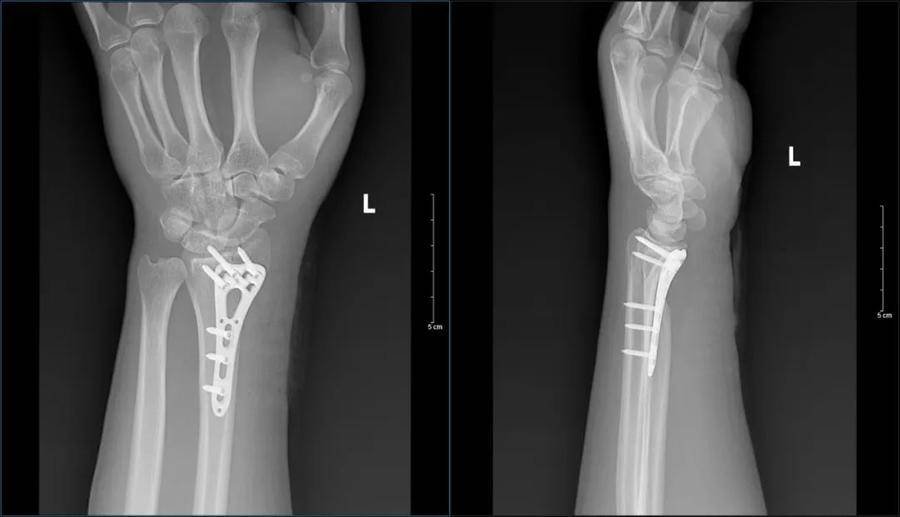

记得那天,伤者因车祸外伤被紧急送入济南南郊医院急诊科,家人焦急万分,伤者痛苦不堪。急诊科医疗团队立即为其进行妥善处置与针对性检查。经过医学影像检查,患者左桡骨远端骨质中断,断端略分离移位,骨折线至桡关节面;左腕其余骨未见明显骨折征象;左腕部软组织增厚呈肿胀表现。

伤者伤情明确,孙焕科主任带领团队迅速制定了详细的治疗方案。经过精心手术——桡骨远端钢板固定,以及术后细致的康复指导,患者不仅伤口快速愈合,而且肢体功能也恢复得十分良好。